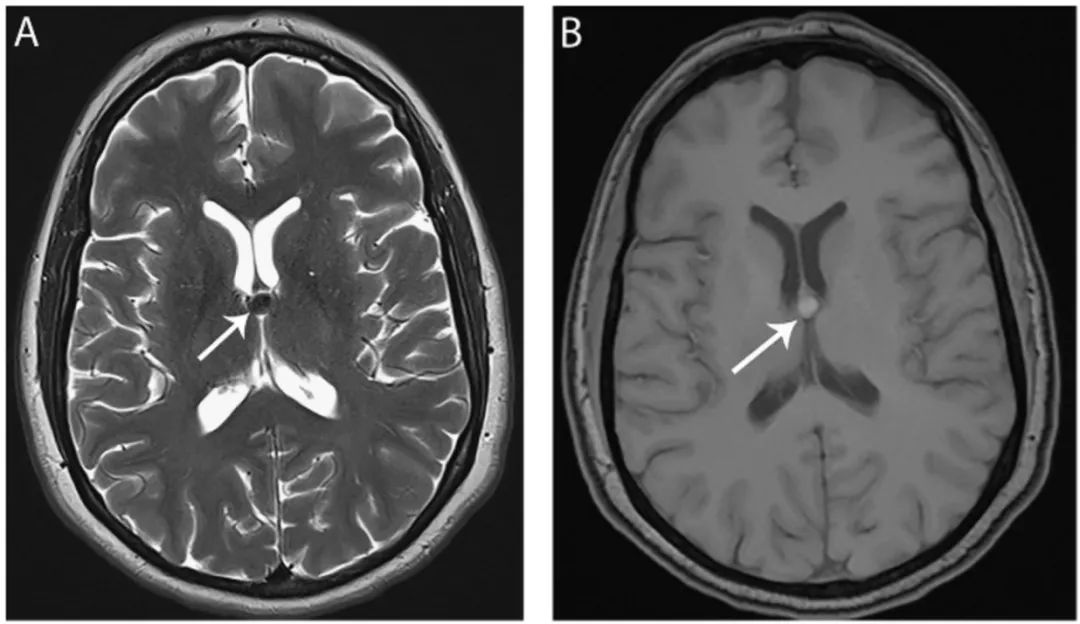

图10 胶样囊肿

轴位T2WI(A)和T1WI(B)显示第三脑室入口水平一个圆形边界清晰的囊肿(箭头),表现为典型的T2低信号和T1高信号。